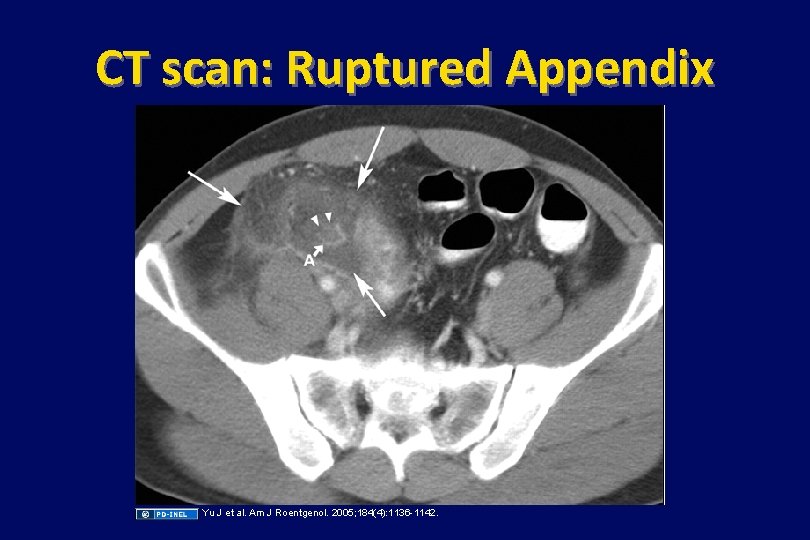

Case (continued) • On post-op day #2, her temp spikes to 38. 6°C. • Blood cultures obtained preoperatively grow E. coli. • She completes a 7 -day course of cefazolin and improves. Since she has no further symptoms and follow-up blood cultures are negative, the antibiotic is stopped. • 36 hours later, her temperature is 38. 8°C and she feels diffuse pain over the site of the appendectomy. • A CT scan of her abdomen reveals a retroperitoneal abscess.

CT scan: Ruptured Appendix Yu J et al. Am J Roentgenol. 2005; 184(4): 1136 -1142.